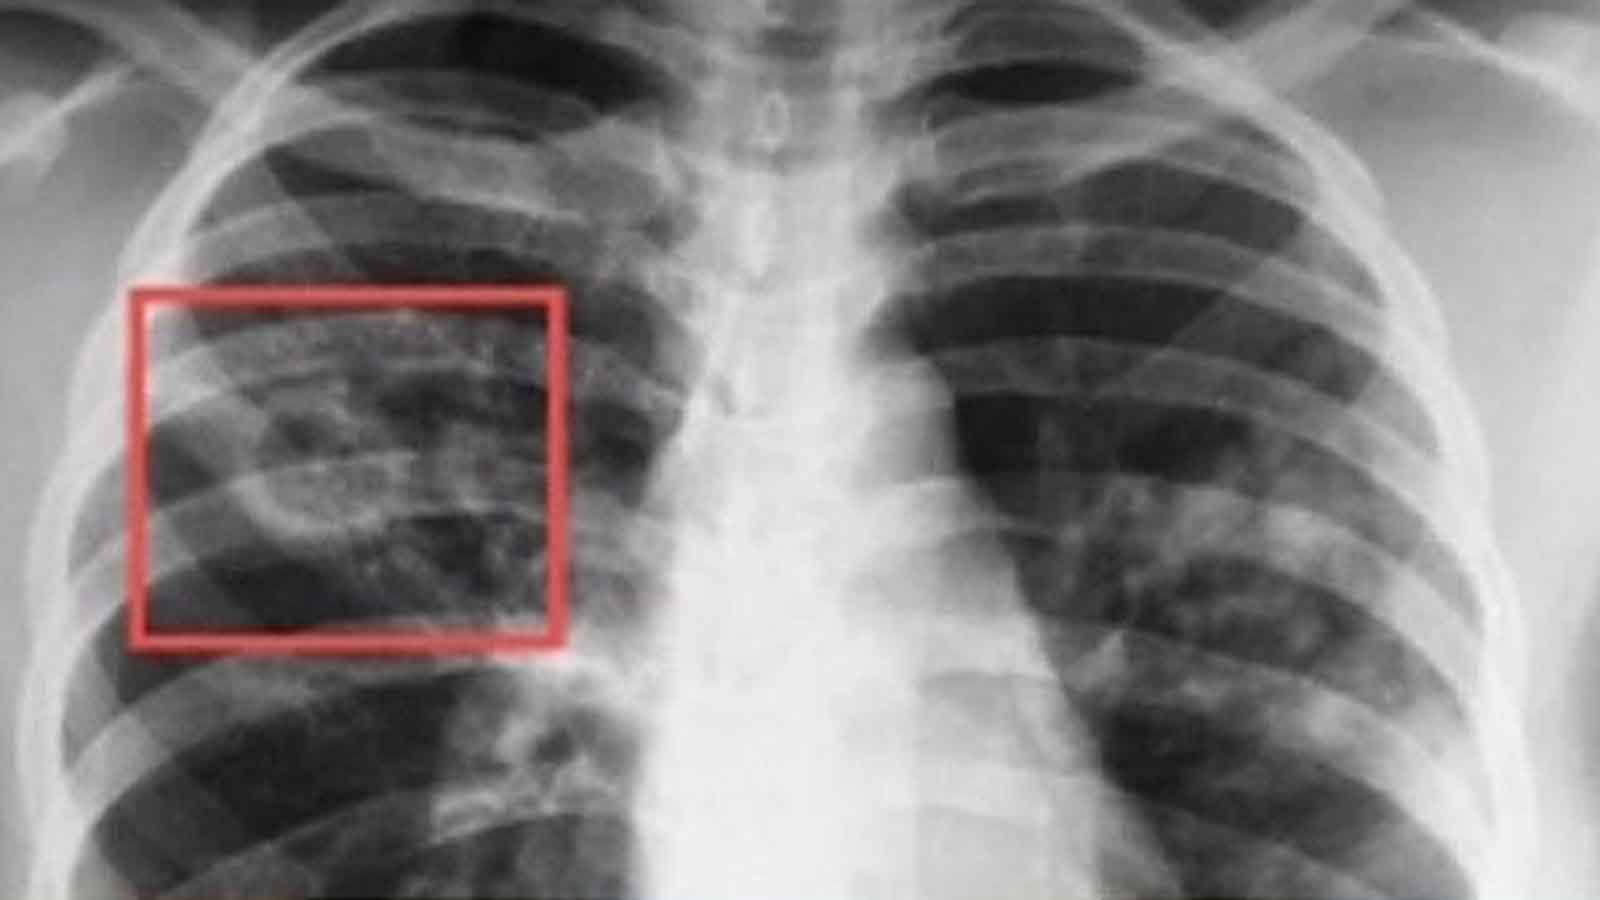

В заключении медработники указывают вероятность развития того или иного заболевания. Локализация патологически изменённой ткани роли не играет, а вот на контуры обращают пристальное внимание. Если они нечётки и очаги более 1 см, то это всегда говорит о злокачественном процессе. При чётких краях можно говорить о туберкулёзе или же новообразованиях доброкачественного характера.

Важную роль здесь играет то, как характеризуются очаги в легких на КТ. С помощью этого вида обследования, основываясь на характерных симптомах, врач может выдвигать предположения о наличии таких серьезных заболеваний, как туберкулез или злокачественные новообразования.

Большое значение уделяется тому, какими являются контуры очагов. В частности, нечеткий и неровный абрис, при диаметре поражения более 1 см, сигнализируют о высокой вероятности злокачественного процесса. Однако если присутствуют четкие края, это еще не является достаточным основанием для прекращения диагностирования пациента. Такая картина часто присутствует при доброкачественных новообразованиях.